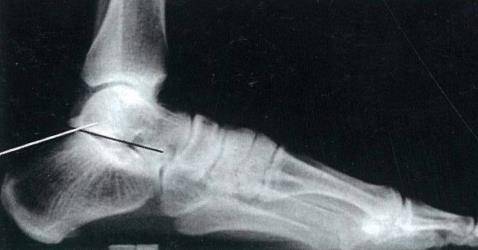

昨天做一例跟骨骨折

201752110265065173_看图王.jpg

微信截图_20160914113859.png